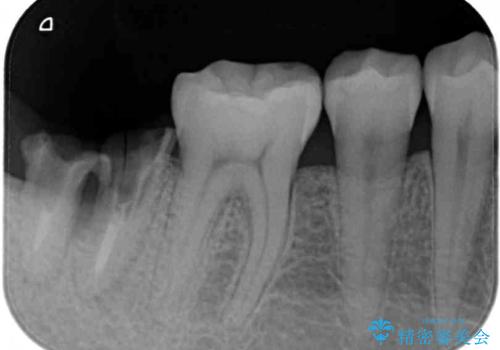

- 左下欠損部のインプラント治療を希望して来院された患者様です。

左下の欠損部を長期間欠損を放置していたことで、咬み合う上の奥歯が動いてしまっていたので、まずは上顎奥歯の部分矯正を行うこととしました。

理想的な咬み合わせに改善した上で、インプラント補綴治療を行うこととしました。

部分矯正を行ったこと治療期間は長くなりましたが、違和感のない咬み合わせを達成することができました。